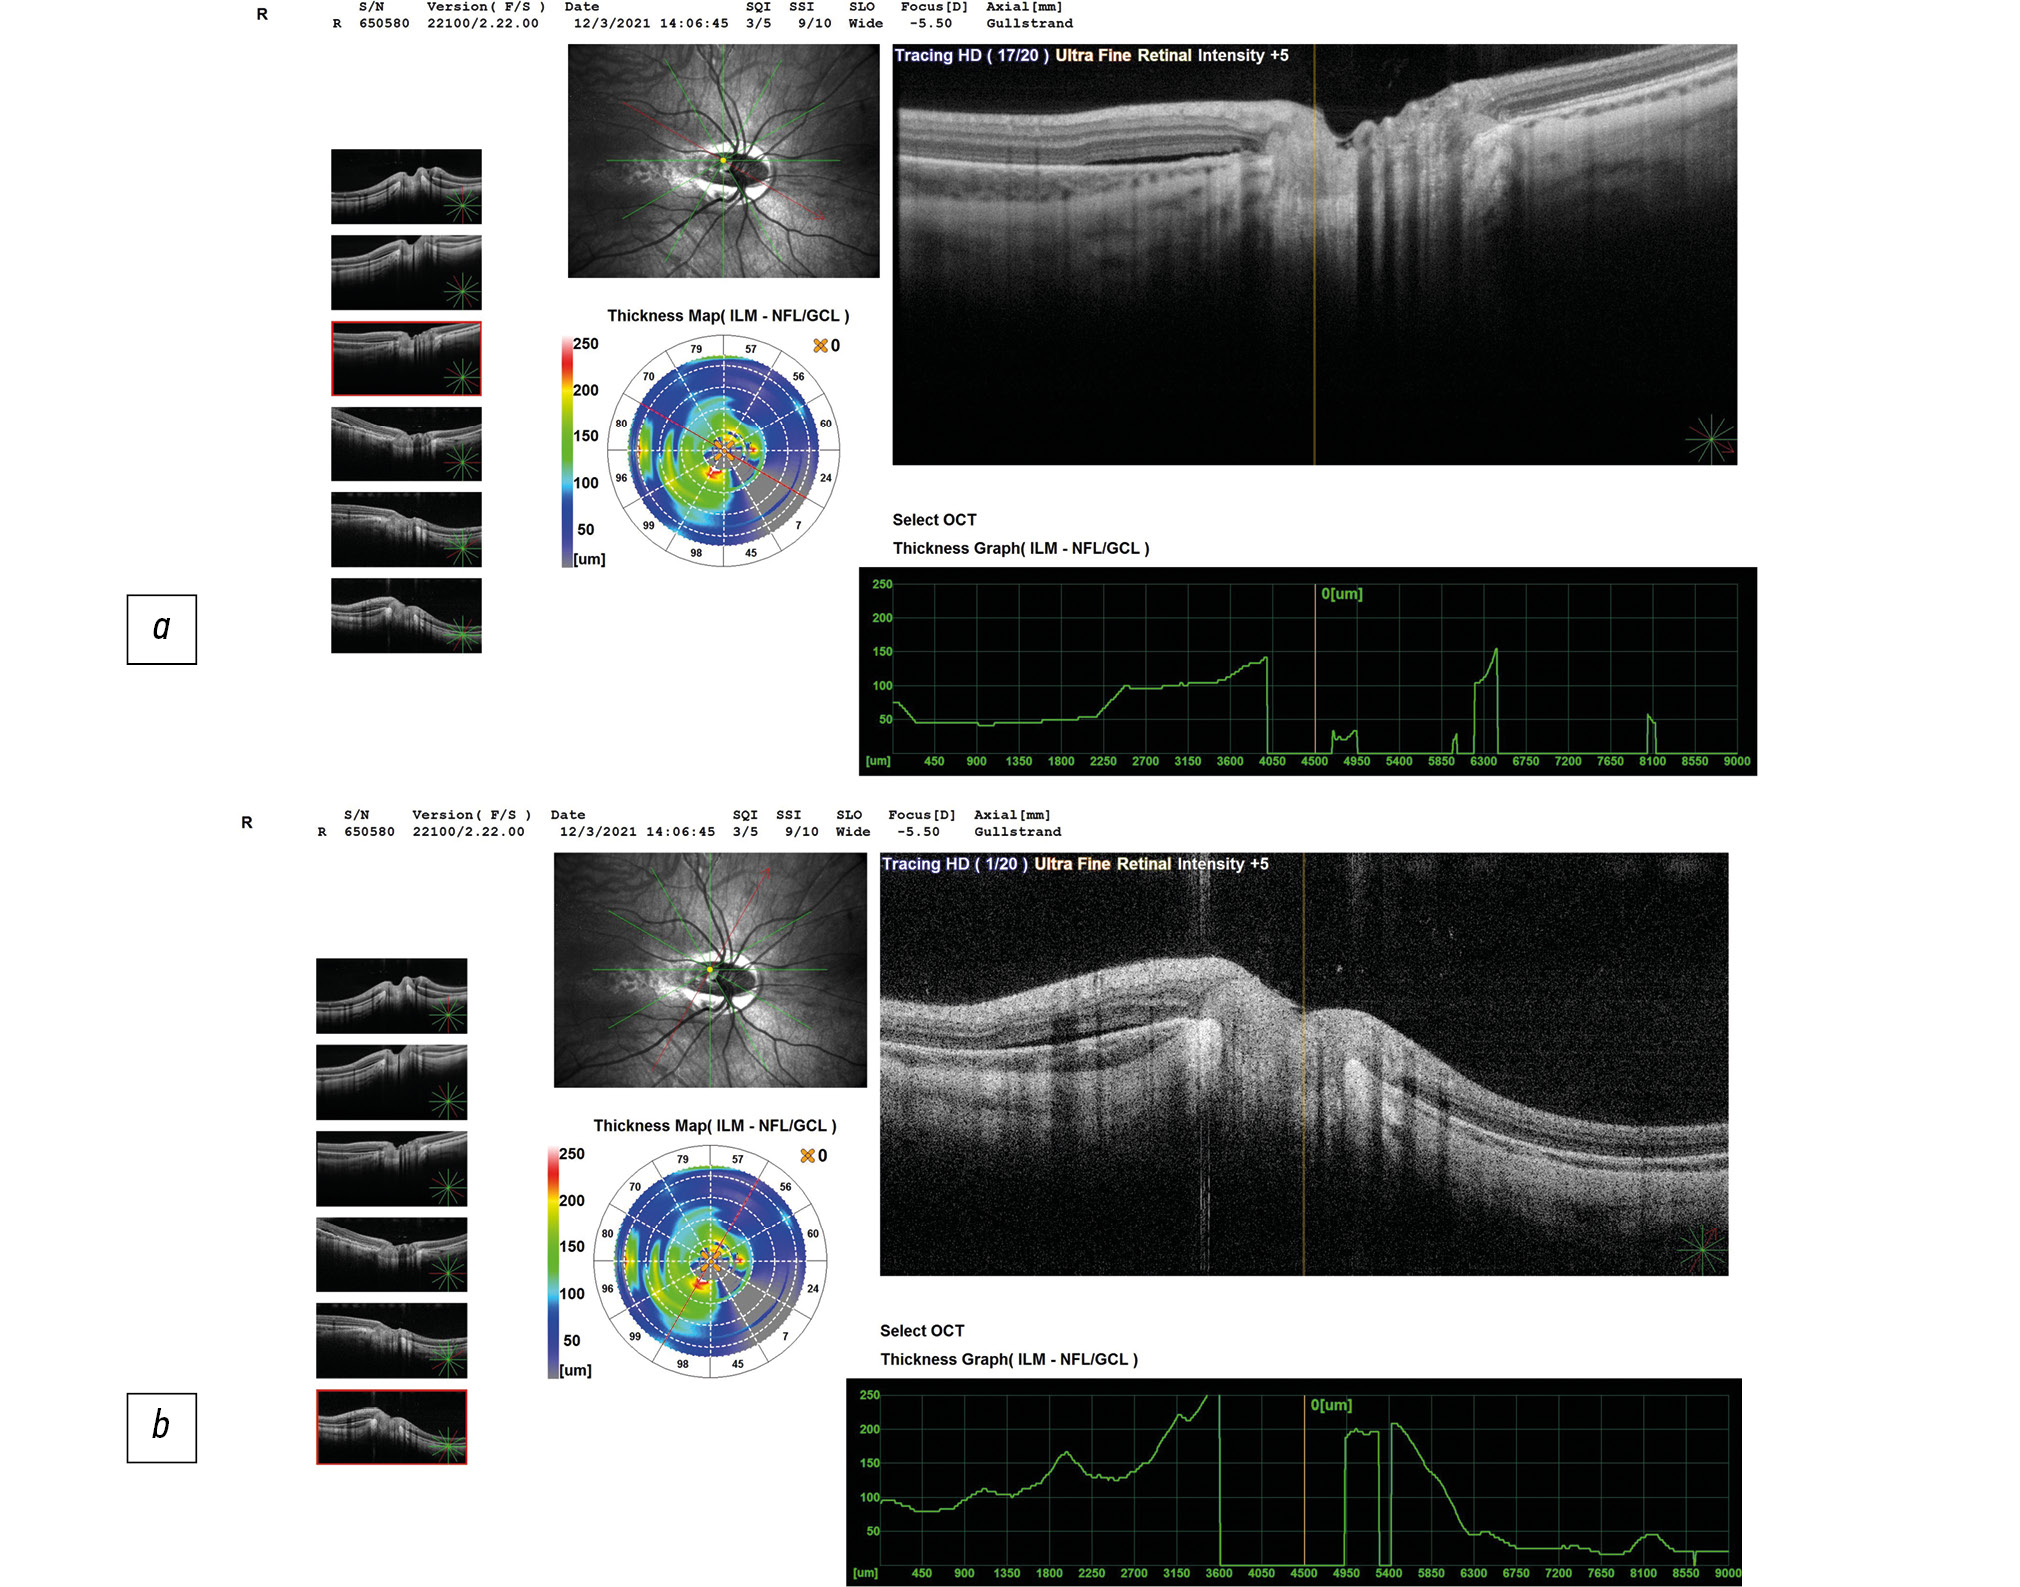

Данные ОКТ макулярной зоны сетчатки правого и левого глаз ребёнка представлены на рисунке 2. Данные ОКТ диска зрительного нерва (ДЗН) правого и левого глаз ребёнка представлены на рисунке 3.

Рис. 3, а, b. ОКТ диска зрительного нерва (ДЗН) правого глаза ребёнка на момент поступления в стационар: экскавация деформирована, расширена, заполнена субстратом однородной рефлективности средней степени, выявляется перипапиллярная щелевидная отслойка нейроэпителия в верхне-височном (а) и нижне-височном (b) квадрантах.

Справа — контур фовеолярной депрессии сглажен, отслойка нейроэпителия в макулярной зоне, деструкция и дезорганизация нейроэпителия и пигментного эпителия, центральная толщина сетчатки (ЦТС) 321 мкм, Слева — структура сетчатки в макуле не изменена, ЦТС 276 мкм. Справа экскавация ДЗН деформирована, расширена, заполнена субстратом однородной рефлективности средней степени, перипапиллярная щелевидная отслойка нейроэпителия в верхне-височном (рис. 3а) и нижне-височном (рис. 3б) квадрантах. Слева — экскавация ДЗН деформирована, расширена.